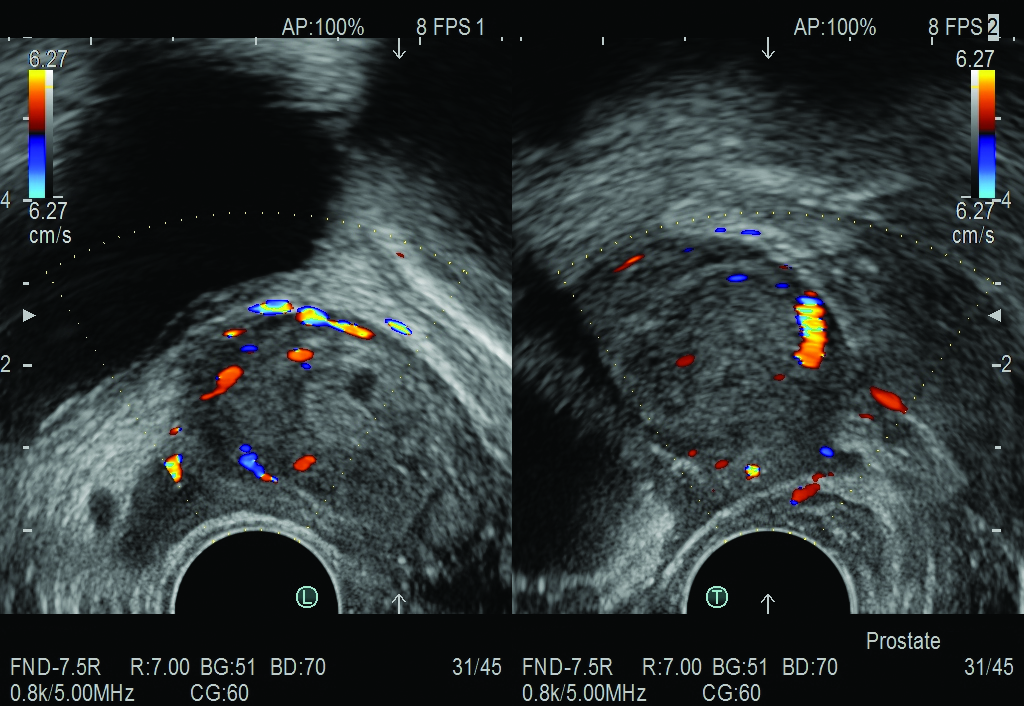

Side-Fire Bi-Plane prostate transducer with simulataneous display and wide scanning, as well as a 200° field of view.